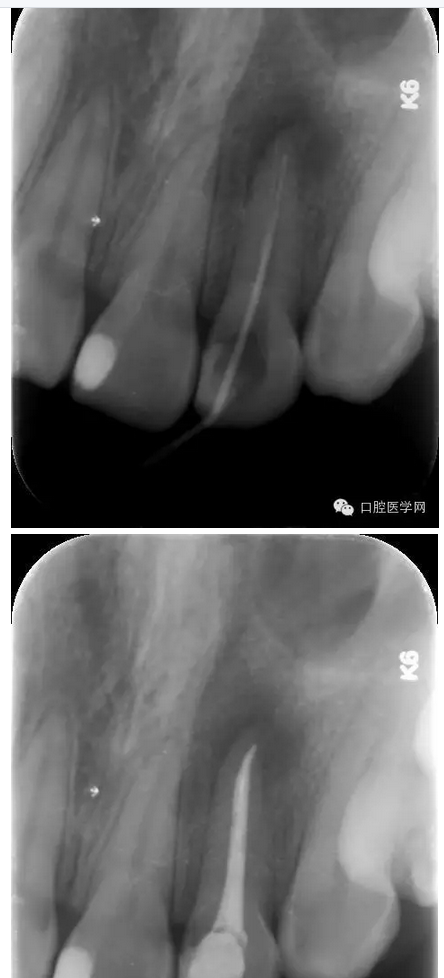

治療:第一次:去舊充填體,去腐質(zhì),GG鉆去除牙膠充填體,疏通根管,測量工作長短,H銼與K銼去除剩余牙膠,雙氧水和鹽水大量沖洗,機擴至S1,超聲蕩洗,激光行根管消毒,封CP球。

第二次:復診無不適,回去后疼痛即刻解除。叩診無不適。無松動。處置:去暫封,見根管內(nèi)無滲出,機擴至F2,雙氧水和鹽水大量沖洗,超聲蕩洗,激光蕩洗加消毒,干燥,封氫氧化鈣。

第三次:復診無不適。叩診無不適,無松動。處置:去除暫封物,鹽水沖洗,試尖,牙膠尖+AHplus糊劑冷測壓充填,玻璃離子體充填。